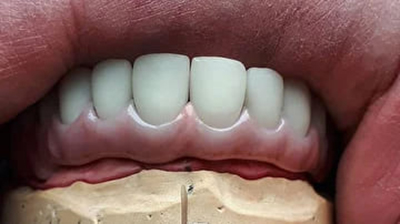

Металлокерамическая коронка выглядит как колпачок, облицованный керамической массой. Готовая коронка надевается на подготовленный зуб. Каркас изготавливается из металлических сплавов. Именно на него приходится вся нагрузка и функция сохранения корня. В нашей клинике металлический каркас изготавливается на немецком цифровом оборудовании с применением 3D технологий. Все происходит автоматически — это гарантирует качественное изготовление каркаса, в отличии от устаревшего способа изготовления методом литья.

Снаружи каркас покрыт слоем керамической массы. По цвету керамика полностью идентична натуральному тону эмали и подбирается индивидуально под каждого пациента.